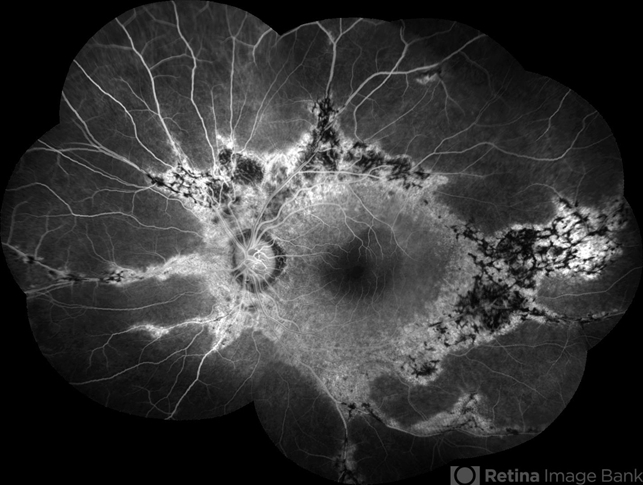

- Female patient, 32-years-old, Asian, appeared at the clinic with a history of glaucoma. 20/20 visual acuity in both eyes. Examination of color photography, pigmentary changes were observed following the vascular arcades only in the left eye. Suggestive of paravenous degeneration.